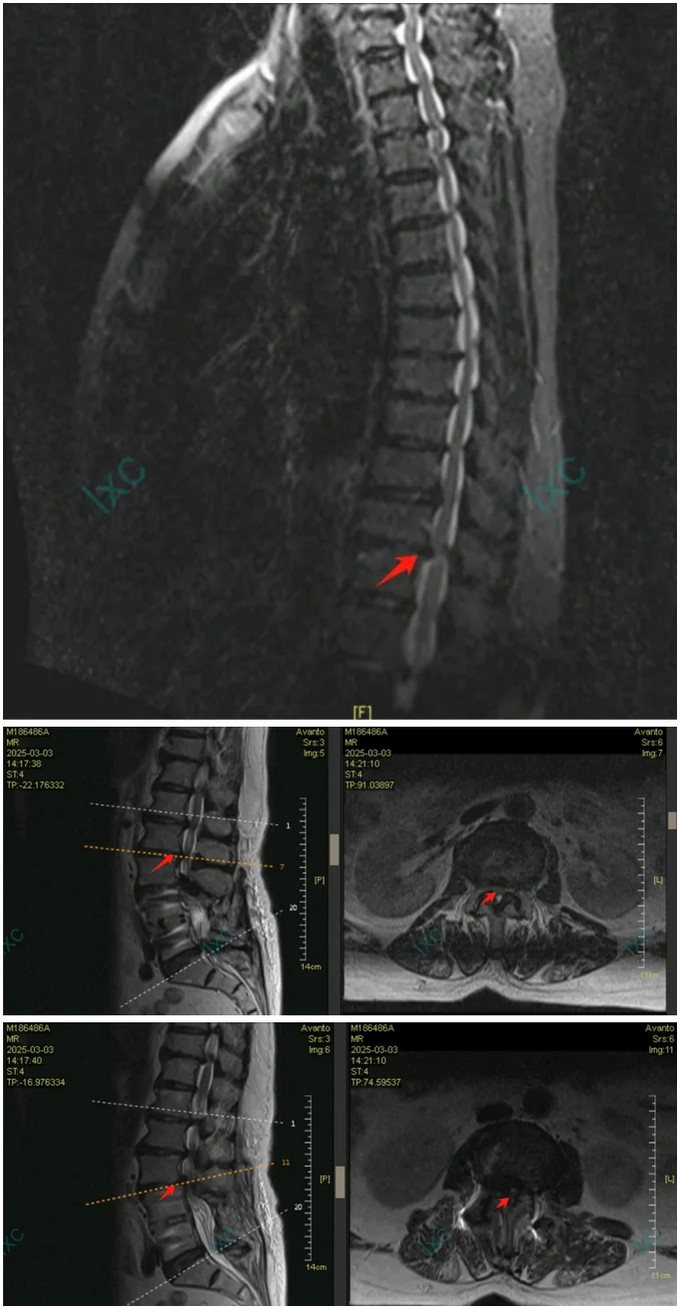

轉(zhuǎn)機出現(xiàn)在今年初春。當邱女士右腳完全癱瘓時,通過港澳醫(yī)療界同行聯(lián)系到我院王榮茂主任,林翔主任團隊接診后,敏銳發(fā)現(xiàn)患者除腰椎問題外,還存在進行性加重的中樞神經(jīng)系統(tǒng)癥狀。“巴氏征陽性、下肢肌力僅1-2級,這提示存在脊髓層面損傷。”林翔主任醫(yī)師回憶初診時的關(guān)鍵判斷。

(胸椎MR顯示T11-12節(jié)段脊髓壓迫特寫,及腰椎鄰椎病變特寫)

多學科會診揭開了“雙重癱瘓”之謎:胸椎T11-12節(jié)段椎間盤突出合并黃韌帶鈣化,已造成脊髓明顯變性;而腰椎鄰椎病變更像是“煙霧彈”。麻醉科王翔鋒主任醫(yī)師采用預存式自體血回輸技術(shù),為高齡患者筑起血液安全防線,為手術(shù)團隊拆彈奠定堅實的后方陣地。